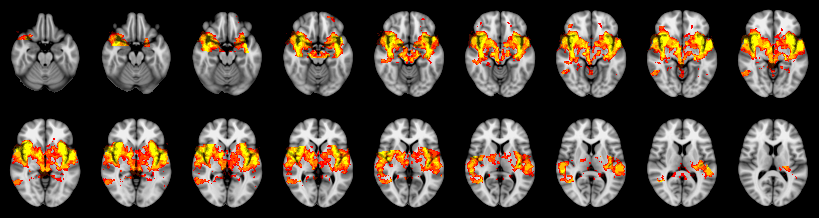

Pain study, TFCE, Uncorrected

Combined

Tippett:

Fisher:

Stouffer:

Edgington:

Mudholkar–George: